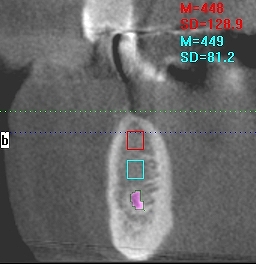

右下4番、インプラント埋入。| |広島市安佐南区の歯科医院 右下4番、インプラント埋入。 トップ お知らせ・ブログ 右下4番、インプラント埋入。 右下4番、インプラント埋入。 Web診療予約 初めての方へ 選ばれ続ける理由 院内設備について 歯が痛いしみる一般歯科 歯がぐらぐらする歯周病 健康な歯を保ちたい予防歯科 子供の虫歯予防をしたい小児歯科 銀歯をセラミックに審美歯科 白い歯を目指しませんか?ホワイトニング 矯正専門医がいるので安心矯正歯科 抜けた歯を補いたいインプラント・入れ歯 医院案内 スタッフ紹介 メリィハウス歯科クリニックオフィシャルホームページ ラベンダー歯科クリニックオフィシャルホームページ お知らせ・ブログ ホーム 診療科目 一般歯科 歯周病治療 予防治療 小児歯科 審美治療 ホワイトニング 矯正歯科 入れ歯・インプラント マウスピース矯正 初めての方へ 院長・スタッフ 設備紹介 医院案内・アクセス メニューを閉じる